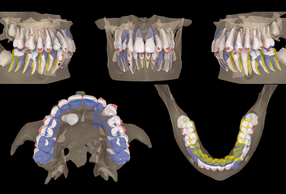

Tuttavia, il protocollo Canine First propone un cambio di paradigma: il recupero del canino prima dei movimenti ortodontici principali per minimizzare i rischi radicolari. Questo case report illustra il trattamento di un paziente di 14 anni mediante l'integrazione di trazione biomeccanica ausiliaria e allineatori trasparenti con pianificazione CBCT-guidata.

- Analisi Radiografica: inclusione bilaterale di 13 e 23 in Settore S5 (mesializzati rispetto alle radici dei laterali) con un angolo α di 76, 66°. La maturazione vertebrale (CS3-CS4) indica una fase post-picco o di fine crescita.

Dopo il recupero palatale, è iniziata la fase con allineatori trasparenti, sfruttando il software ClinCheck® Pro e l'integrazione dei dati della CBCT.

Pianificazione e criticità

- Torque: necessità di recuperare il torque positivo sugli incisivi superiori.

- Classe: correzione sagittale tramite distalizzazione sequenziale ( per creare spazio ai canini) e Jump sagittale.

- Gestione del 23: utilizzo di un attachment rettangolare (secondo protocollo Capuozzo et al.) per migliorare il controllo del torque durante la traslazione palato-vestibolare.

- Gestione del 13: data la posizione estremamente palatale, inizialmente non è stato incluso nell'allineatore. È stato avvicinato alla corretta posizione vestibolare mediante un elastico a cavaliere.

L'integrazione tra la biomeccanica tradizionale (leve in TMA) e l'ortodonzia digitale (allineatori e CBCT) permette di gestire casi complessi di inclusione con estrema sicurezza. Il protocollo Canine First si conferma una scelta vincente per minimizzare i rischi iatrogeni, mentre la tecnologia ClinCheck® Pro garantisce una predicibilità altrimenti difficile da ottenere in casi di II Classe Divisione 2.